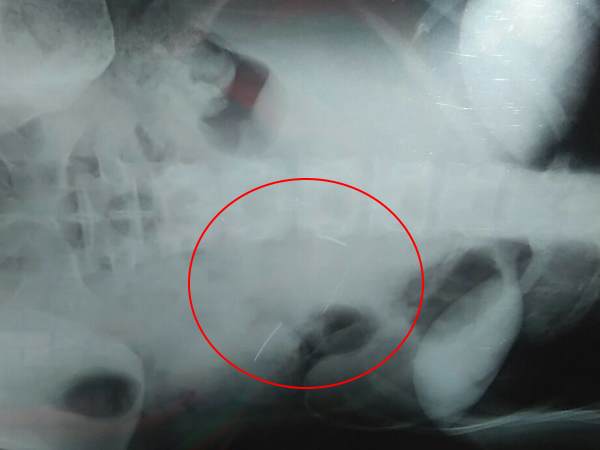

वाराणसी। वैसे तो आपने डॉक्टरों की लापरवाही के कई किस्से सुने होंगे लेकिन जो लापरवाही हम आपको बताने जा रहे हैं उसे सुनकर आपके भी होश उड़ जाएंगे। मामला पूर्वांचल के एम्स कहे जाने वाले काशी हिंदू विश्वविद्यालय के सर सुंदरलाल अस्पताल से जुड़ा है जहां एक महिला की नसबंदी के ऑपरेशन के बाद डॉक्टरों ने लापरवाही करते हुए महिला के पेट में एक दो नहीं बल्कि पांच सुई छोड़ दी। गलती का एहसास होने के बाद डॉक्टरों ने दो सुई तो निकाल दी है लेकिन 3 अभी भी महिला के पेट में हैं जो महिला की जिंदगी के लिए खतरा बन चुकी है।

ऑपरेशन के कुछ दिन बाद पत्नी के पेट में दर्द की शिकायत रहने लगी। उसने अपनी पत्नी को वापस प्रसूति विभाग की हेड को दिखाया जहां एक्सरे में पता चला कि पेट में डॉक्टर की लापरवाही से 5 सुई अन्दर ही रह गयी है। पति ने आरोप लगाया कि यह पता चलते ही डाक्टर ने हमें धमकाया और चिकित्सालय के ही एक दूसरे डाक्टर के पास भेज दिया जिन्होंने मेरी पत्नी का ऑपरेशन किया। पति ने बताया कि डॉक्टर ने पहले हमसे वादा किया कि वो सारी सुई निकाल देंगे पर उन्होंने सिर्फ 2 ही सुई निकाली और 3 पेट में ही छोड़ दिया तथा हमें वहां से भगा दिया। इसके बाद मेरी पत्नी की तबियत खराब रहने लगी। हमने थक हारकर आज न्याय दिलाने की लंका थाने में तहरीर देकर गुहार लगाई है।